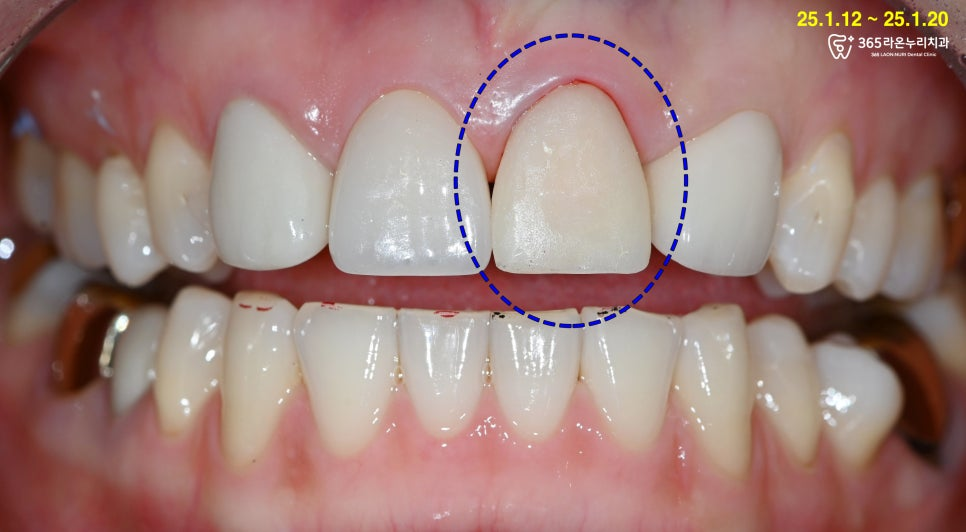

정면에서 왼쪽 앞니가

깨져 나간 것을 확인할 수 있었습니다.

엑스레이 촬영 및 진단 사진을

촬영 이후 영구치가 신경 부근까지

파절되지는 않았으나

재제작이 필요하다는

설명을 드렸습니다.